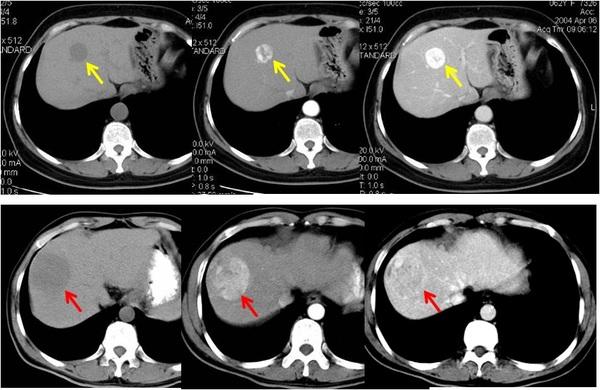

肝血管瘤影像,肝癌影像

肝脏丨血管瘤_影像

ct肝海绵状血管瘤

肝血管瘤ct

肝血管瘤图片